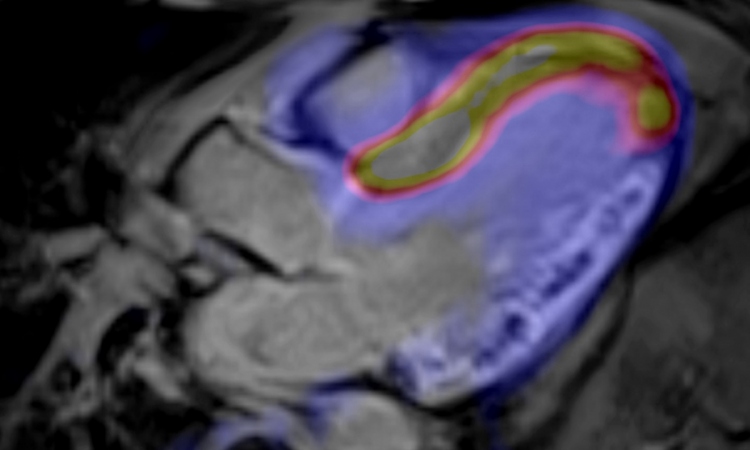

Even more is happening in PET/MRI, i.e. the combination of positron emission tomography and magnetic resonance tomography. "PET and MRI are still in their 'honeymoon period'," Professor Vivky Goh, Chair of Clinical Cancer Imaging at King’s College London, points out, although she can also see a shift in paradigm. ‘The times where we simply used to measure whether a tumour has grown or shrunk are over. Now we actually have access to the biology of the tumour.’

‘The availability of PET/MRI opens up new possibilities in oncological radiotherapy,’ confirms Professor Ursula Nestle, of the Department for Diagnostic and Therapeutic Radiology at the University Hospital Freiburg (Germany): ‘The hybrid procedure facilitates very precise therapy planning.’ This applies in particular to tumours which can only be visualised with difficulty with CT but very well visualised with MRI and which can also be examined very well with PET, such as those found in the upper abdomen, prostate and brain.’ Nestle is expecting a lot from the combination of molecular PET and molecular MRI.

Recently launched is a new EU breast cancer research project, ‘Digital Hybrid Breast PET/MRI for Enhanced Diagnosis of Breast Cancer’ (HYPMED). The European Institute for Biomedical Imaging Research (EIBR) runs this, as project coordinator, and the University Hospital Aachen, Germany is scientific coordinator. The project envisages the integration of a PET detector into an MRI surface coil so that high resolution PET imaging and high resolution MRI imaging can be carried out synchronously in breast cancer patients – including the opportunity to carry out minimally invasive MRI- and PET-guided biopsies. ‘This approach is basically aimed at upgrading any conventional MRI scanner into a high resolution PET/MRI system,’ confirms Professor Volkmar Schulz Dr-Ing, from the Institute for Experimental Molecular Imaging at University Hospital Aachen.